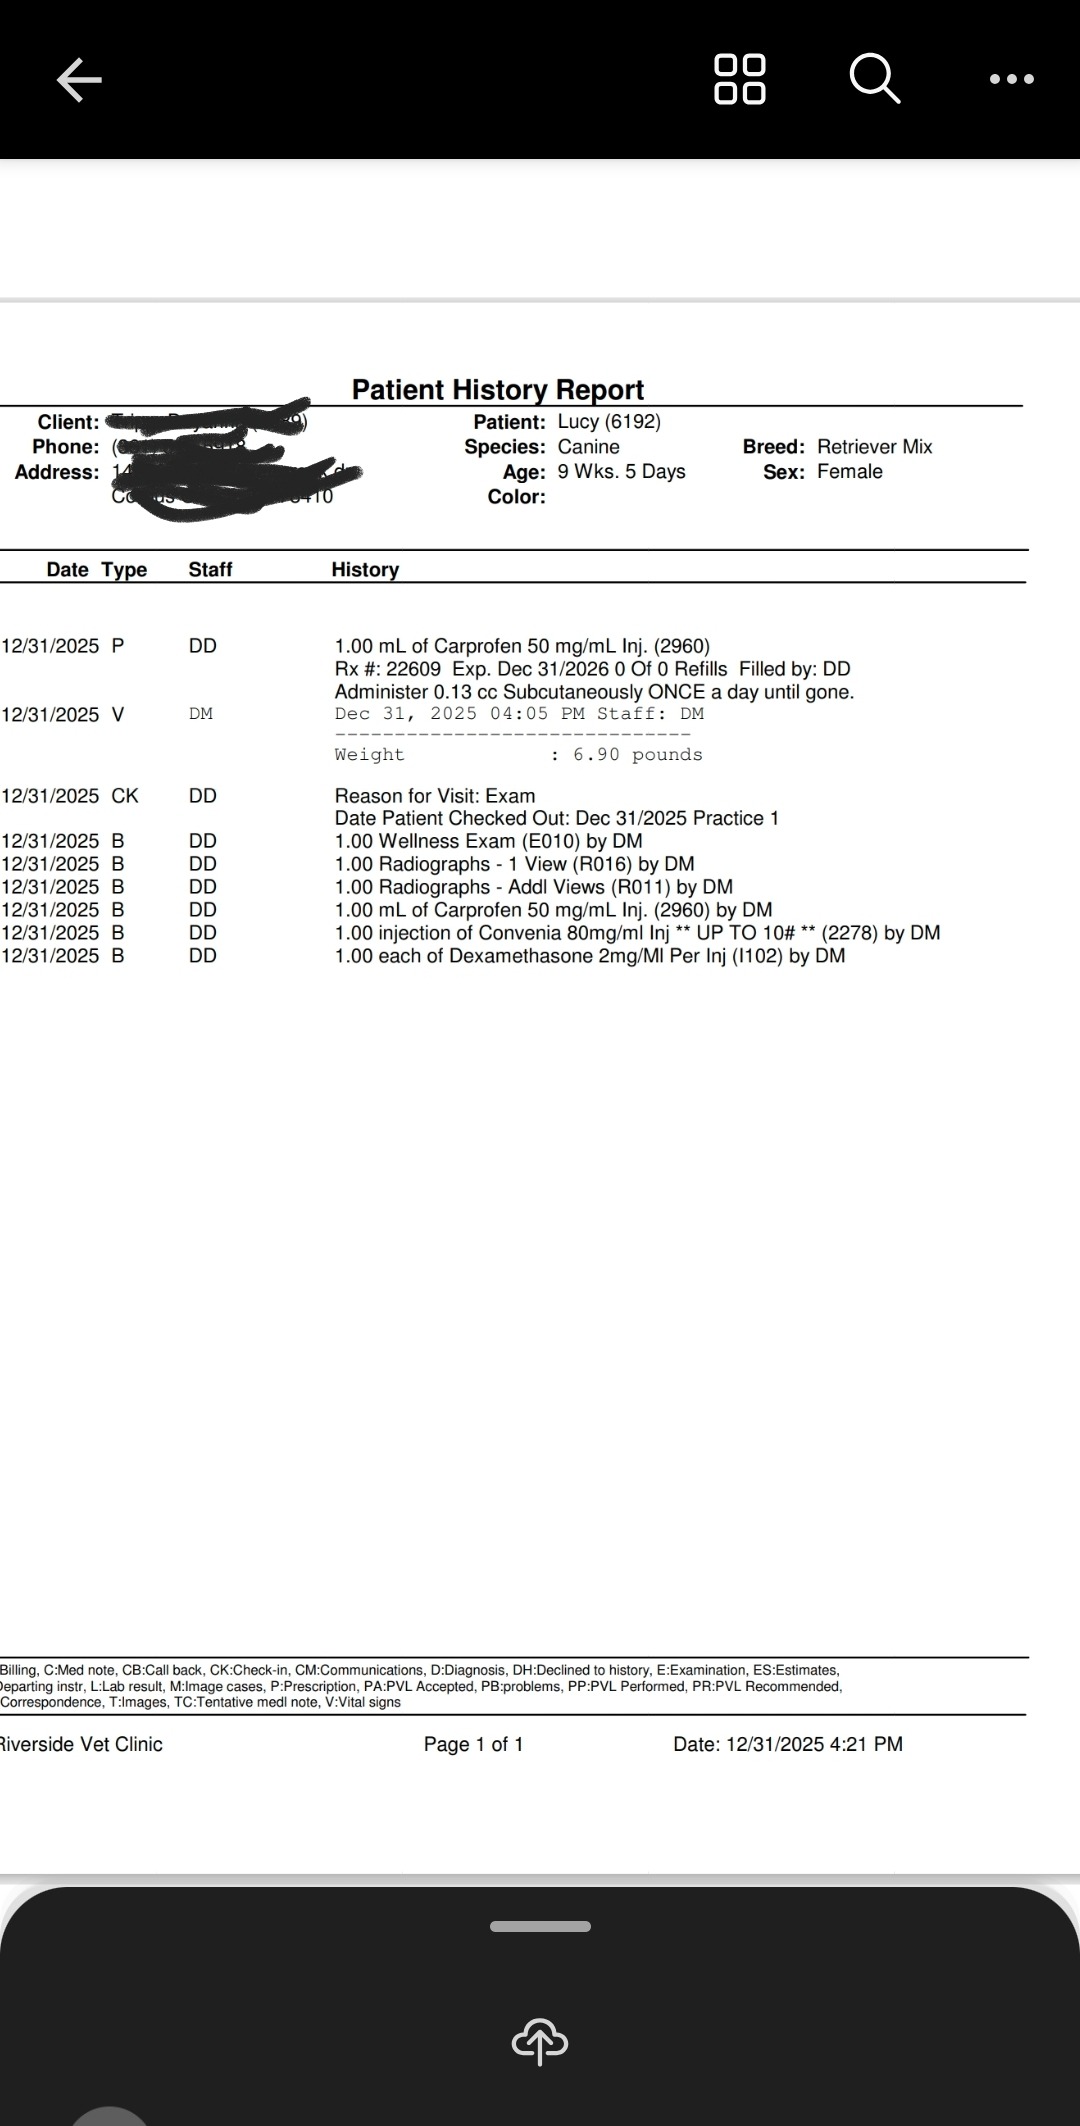

I'm Deyanna Tripp. I rescued two puppies from being euthanized, and one of them had been hit by a car and had a broken leg. Turns out, she has a diaphragmatic hernia and she needs emergency surgery. She is only breathing with one of her lungs. She's currently on steroids, antibiotics, and pain medicine. Any help is appreciated as this was not expected at all, and we just want to save this poor little girl. Her name is Lucy and her and her sister are only 9 weeks old.